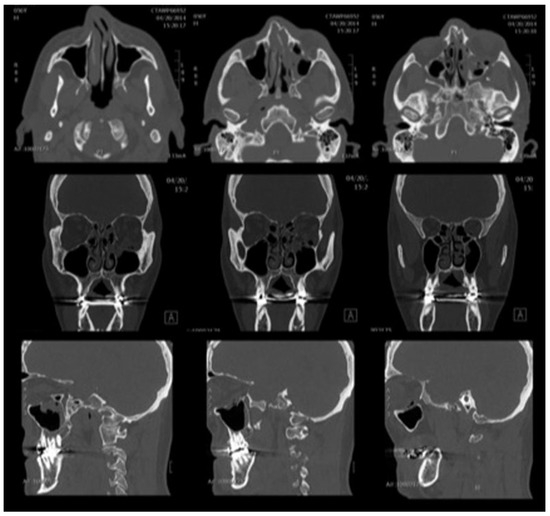

The patient was taken emergently (within 40 min of symptom onset) to the operating room for orbital decompression and hardware removal (no imaging was obtained at this time due to the clear clinical diagnosis and necessity of urgent operative management). This was accomplished via the same transconjunctival incision with an additional lateral canthotomy. Intraoperatively, there was no evidence of intraorbital hematoma, active hemorrhage, or old clot. The orbital floor plate was removed, and a portion of the orbital floor and medial wall excised to aid with decompression. Postoperative imaging was notable for removal of the hardware and bony decompression, without evidence of retrobulbar hemorrhage, but mild proptosis of the left globe (Figure 4). The optic nerve was noted to mildly stretched, secondary to intraorbital edema.

Figure 4. Postdecompression computed tomography. There has been interval removal of the orbital floor implant and some of the bony floor, with significant edema and proptosis of the left globe.